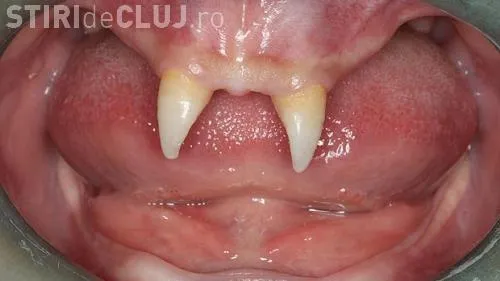

Un băiat din China i-a uimit pe medici, după ce i-au crescut doi canini foarte ascuţiţi, neavând alţi dinţi în gură.

Medicii i-au spus că cei doi canini vor fi operați când va fi un adult și că totul va costa 10.000 de euro. ”Nu are prieteni şi își dă din ce în ce mai mult seama cât de diferit este faţă de ceilalţi copii”, a spus mama copilului, care a adăugat că fiul ei a devenit mai izolat şi agresiv cu colegii, conform rtv.net.